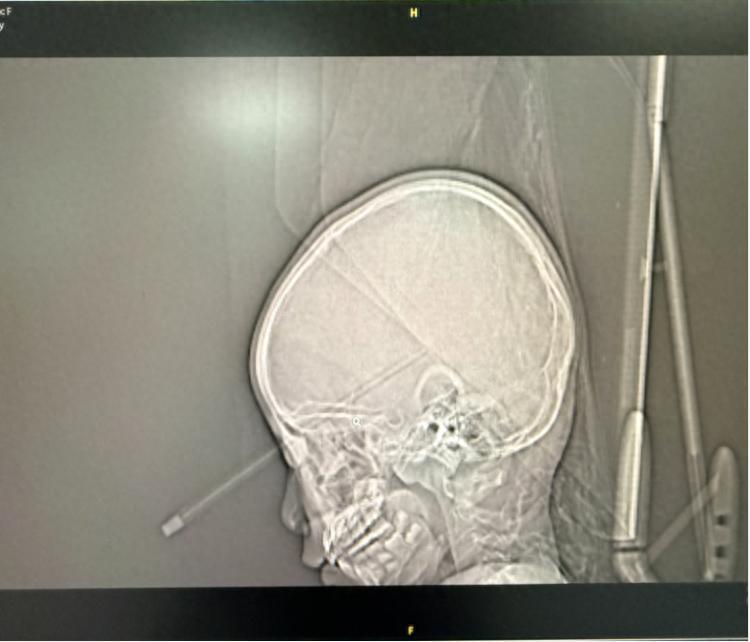

影像检查显示配资114,铅笔从女孩眼中深入脑部。重医附属儿童医院供图

该院重症医学科主任符跃强介绍,受伤的小女孩不慎将铅笔刺入右眼眶内上缘后,在家附近的医院进行了紧急处理,随后家长将她送到重庆医科大学附属儿童医院。经过急诊CT检查发现,铅笔从女孩右眼眶鼻上缘刺进去,并穿破眼眶骨头,一直扎到大脑里,引发了眼眶骨折、眼眶周围软组织肿胀、颅内出血及积气等一系列严重并发症,病情十分凶险,稍有延误便可能危及视力甚至生命。